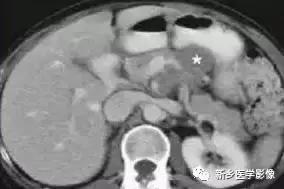

2.影像学诊断:胰腺淋巴瘤在影像学上两种表现形式 :(1)病变弥漫侵润, 表现为胰腺增大;(2)胰腺内边界清晰的限局性的肿块。肿瘤一般均质, 密度低, T 1WI 上信号低于正常胰腺, T 2WI 上信号略高于正常胰腺, 增强扫描示病变乏血供。病变区罕有坏死、出血或钙化。在腹膜后及腹腔内可有肿大淋巴结。部分患者可有胆管扩张。